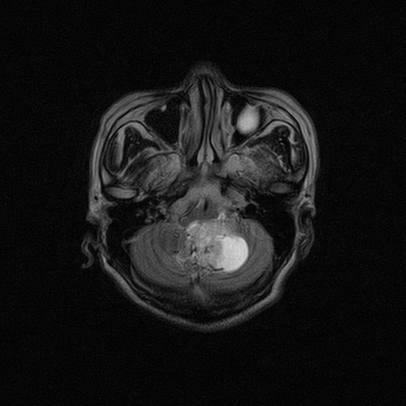

标题: MRI2064:少见病例。男性52,视力下降多年。 [打印本页]

标题: MRI2064:少见病例。男性52,视力下降多年。

四脑室区见混杂信号占位影,脑室系统扩张明显,临近结构显著受压称位,患者52岁,多考虑室管膜瘤可能性大

考虑第四脑室室管膜瘤并阻塞性脑积水。

应该是来源于小脑蚓部的占位,如血管母细瘤或星形细胞瘤

小脑血管母细胞瘤.并外压性脑积水.

小脑蚓部胶质脑膜瘤突入四脑室;肿瘤内见血管流空信号和钙化信号.

比较典型的脉络丛乳头状瘤并脑积水,鉴别小脑蚓部血管母细胞瘤。